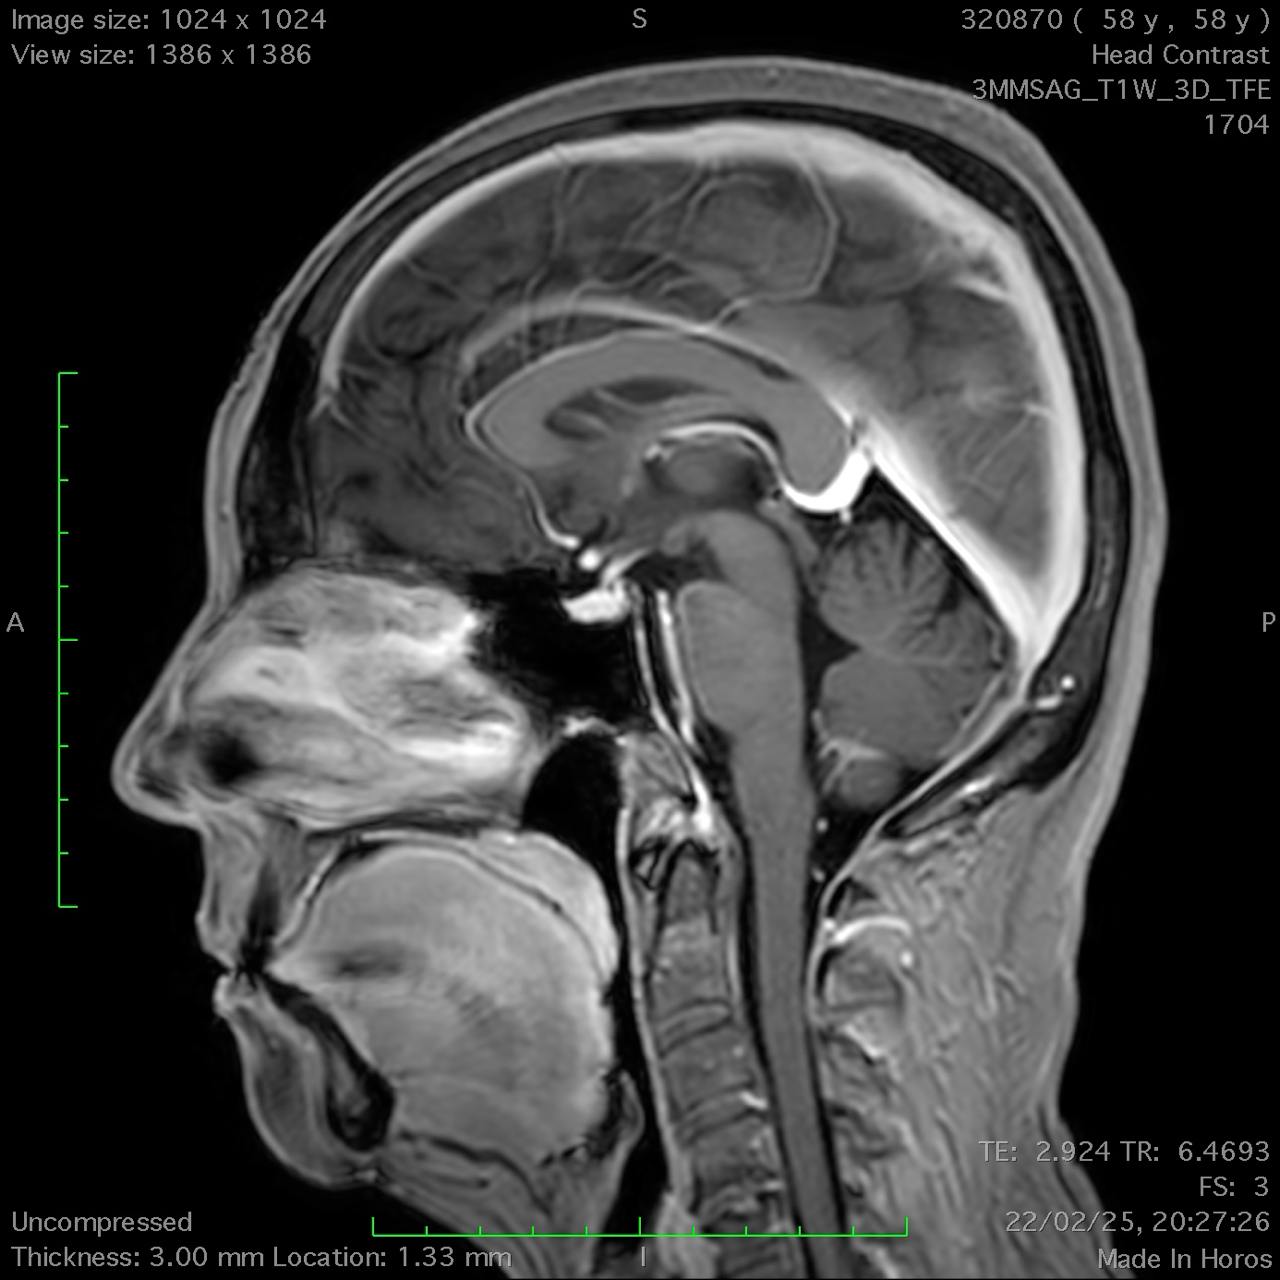

Results: Cerebellar ataxia, bilateral lower limb sensory loss, absent deep tendon reflexes, and marked bidirectional nystagmus were all found during the neurological test. Bilateral vestibular areflexia was established by video head impulse testing (vHIT). Electroneurography demonstrated sensory neuronopathy, and brain MRI showed mild cerebellar atrophy, particularly in the vermis, without evidence of central demyelination or structural abnormalities suggestive of other neurodegenerative conditions. The diagnosis of CANVAS was highly supported by the combination of clinical, electrophysiological, and imaging evidence, even if genetic confirmation was not feasible due to financial constraints CANVAS.

Conclusion: Suspicion of CANVAS should be raised in the presence of bilateral vestibular impairment, sensory neuropathy, progressive ataxia, and severe bidirectional nystagmus. The diagnosis is further supported by moderate cerebellar atrophy seen on MRI. When genetic testing is not available, a diagnosis can nevertheless be made using clinical and paraclinical findings, even though genetic testing is the gold standard for confirmation. Patient care can be enhanced, and needless treatments can be avoided, by recognizing CANVAS.

Sagittal T1-weighted MRI (T1W).